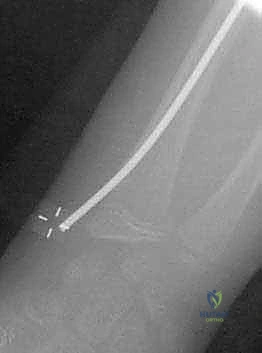

1. تقنية المسامير النخاعية المرنة (Métaizeau Technique / TENs)

تُعد هذه التقنية ثورة في جراحة عظام الأطفال، والأستاذ الدكتور هطيف من رواد تطبيقها في اليمن.

* الفكرة: بدلاً من فتح المرفق، يتم إجراء شق صغير جداً (لا يتعدى 1 سم) عند منطقة الرسغ (أسفل الكعبرة).

* يتم إدخال مسمار تيتانيوم مرن (Titanium Elastic Nail) داخل التجويف النخاعي لعظم الكعبرة، ودفع المسمار للأعلى حتى يصل إلى منطقة الكسر في المرفق.

* يتم استخدام طرف المسمار المنحني كـ "أداة دفع" لرفع رأس الكعبرة المكسور وإعادته إلى مكانه التشريحي الصحيح بدقة متناهية تحت جهاز الأشعة (C-arm).

* المزايا: لا يوجد فتح جراحي في المرفق، الحفاظ التام على التروية الدموية، ندبة شبه معدومة، وسرعة فائقة في التعافي.

صورة توضح دخول المسمار المرن عبر التجويف النخاعي لرد الكسر من الداخل دون المساس بمفصل المرفق.